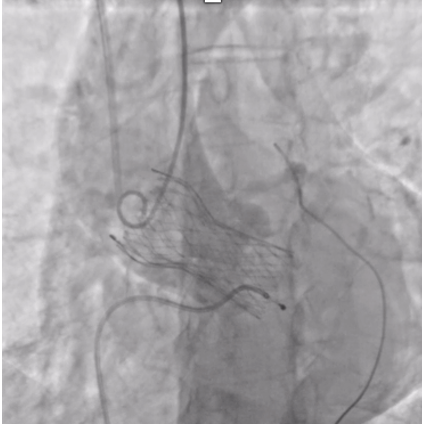

The patient was planned for transfemoral TAVI. Both left and right femoral arteries were punctured under ultrasound guidance. A temporary pacemaker (TPA) was placed in the right ventricle via the left femoral artery, and the right femoral artery sheath was upgraded to the 14Fr sheath. Selective left coronary angiography revealed normal coronaries. Through the right femoral artery, a snare was deployed in the abdominal aorta. The native bicuspid aortic valve was crossed with an Lunderquist wire, which was advanced into the left ventricle. Using pigtain, angiographic gradient was measured, showing severe aortic stenosis. Predilatation was performed using a 20 mm Z-MED balloon with satisfactory results. The TAVI valve, a self-expanding valve, was advanced across the native valve with the aid of the snare and positioned accurately in the cusp-overlap view. Under rapid pacing, the valve was deployed up to 80%, and after confirming satisfactory depth, full deployment was completed in the coplanar view. Final angiographic assessment showed no paravalvular leak (PVL) or aortic regurgitation (AR), with valve depth of 4–5 mm at the NCC and 6–7 mm at the LCC. Femoral closure was performed successfully without vascular complications.